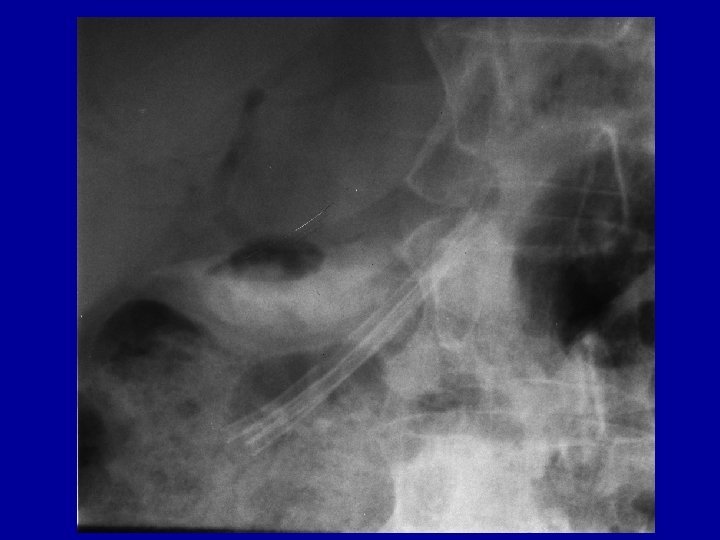

Case report V. • 2004. Okt. ERCP: suprapapillary stricture of common bile duct with normal outflow at the choledocho-duodenostomy, P. divisum • Patulous secondary papilla with suprapapillary stenosis of the dorsal duct • Secondary papillotomy with needle-knife, dilation + 8 F pancreatic stent with jejunal feeding tube. • 2004 Nov. dilation + 10 F pancreatic stent into the dorsal duct (double stenting 8 F + 10 F)

Case report VIII. • 2010 Febr. ERCP: Pancreas divisum with unequivocal changes in the ventral ducts. • Patulous secondary papilla with suprapapillary restenosis and distal dilatation of dorsal duct, • Dilation, 10 F pancreatic stent + 5 F nasopancreatic catheter with citrate lavage for 3 days followed by another 10 F stent placement into the dorsal duct

Case report IX. • 2010 Apr. another 10 F pancreatic stent to calibrate stenosis equilibrating prestenotic dilatation (10 mm=3 x 10 F), • no pain at dilation and further on. • Planned removal after 6 month

Rational for multiple stenting • Patency increased by multiplying internal diameter of stents + space between outer surface and ductular wall • Free outlet of branch ducts assured by space between stents and the ductular wall • Definitive calibration of stenosis to 2/3 of the distal dilatation

Biliary and pancreatic stents in the corresponding ducts Pancreatic lavage with citrate (1. 9%) at 1 -2 ml/min for 3 -5 days